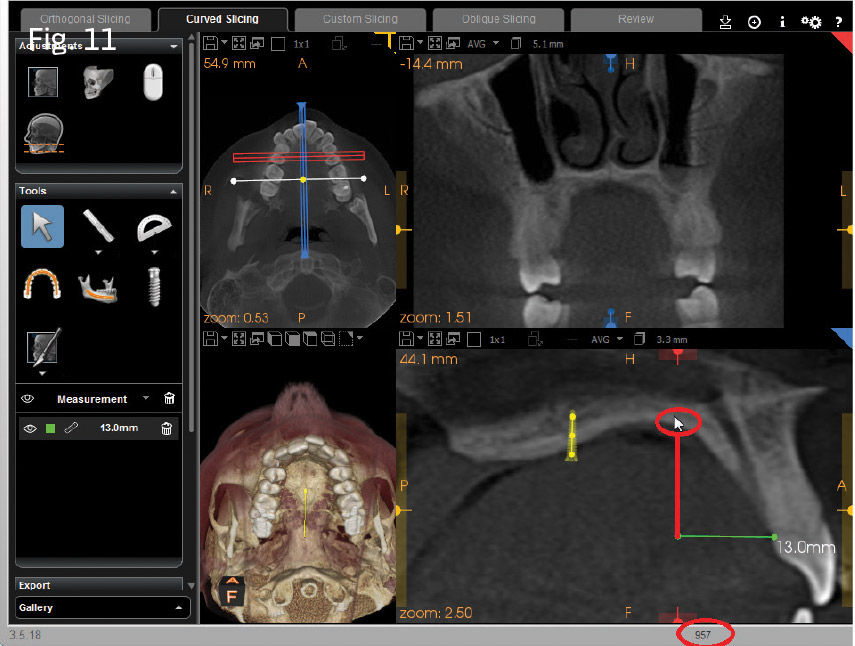

Using CS 3D Imaging simulation software, I hovered the mouse pointer over the buccal shelf of the mandible, as well as the anterior palate, approximately 13mm from the gingival margin of the upper incisors, and observed the relative density value in the lower-right corner of the screen (Figs. 10 and 11). I made note of the values of these individual locations. The buccal shelf represents probably the most dense area of bone for the individual patient in the maxillomandibular complex. The anterior palate and just off the midline allows for assessment of palatal bone values relative to the buccal shelf. With both of these comparisons in mind, I assessed the possible insertion sites at the direct midpalatal suture at the midmesio/distal of the upper first molars, versus the adjacent paramedian locations from the simulated insertion. I made a decision whether to insert a single miniscrew for molar intrusion, instead of two miniscrews at the adjacent paramedian locations.

In Case 1, a collimated CBCT view of the maxilla was captured with a Carestream Dental CS 9300. A miniscrew placement simulation was performed, showing excellent bone density at the midpalatal suture, allowing for a single miniscrew and dumbbell (see Fig. 4). In Case 2, a similar simulation was also performed; both quality and quantity of bone were assessed. It was determined that a single midpalatal miniscrew at the midpoint of the suture would be less reliable than two paramedian miniscrews. The density-gradient tools of the miniscrew placement simulation showed an acceptable gradient of relative bone density in two paramedian locations, rather than a single screw placed in the midpalate.